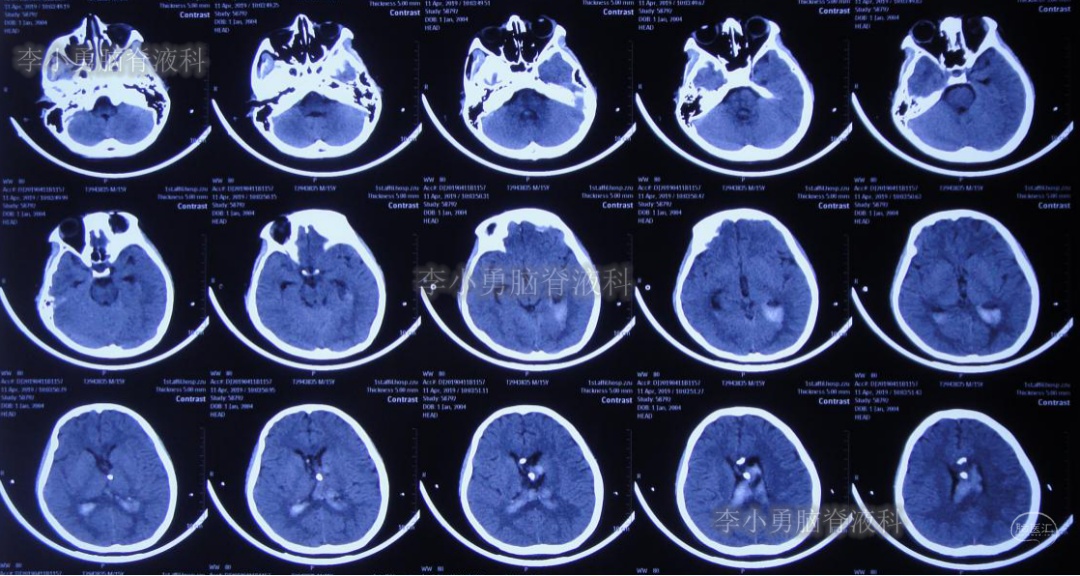

入院当日行头颅CT(图-10):脑室内“动脉瘤切除术”后改变,术区可见引流管影,脑室扩大。

图-10:2019年5月7日头颅CT:引流术后,脑室扩大

入院次日即2019年5月8日,进行了右侧脑室外引流术,并保留原来脑室外引流管(注:脑室内有两根管)。术后常规复查头颅CT(图-11)。

图-11:2019年5月9日头颅CT:引流出淡黄色脑脊液

图-12:2019年5月16日复查头颅CT:左侧颞角扩大并周边水肿

图-14:2019年5月28日头颅CT:脑室较前缩小,水肿亦减轻

但是患者逐渐开始出现头部不适,轻度头痛,且近期记忆力很差。右侧脑室外引流术后25天即2019年6月3日,再次复查头颅CT(图-15):右侧颞角再次扩大并周边水肿明显,术区水肿。

图-15:2019年6月3日头颅CT:左侧颞角扩大并周围水肿